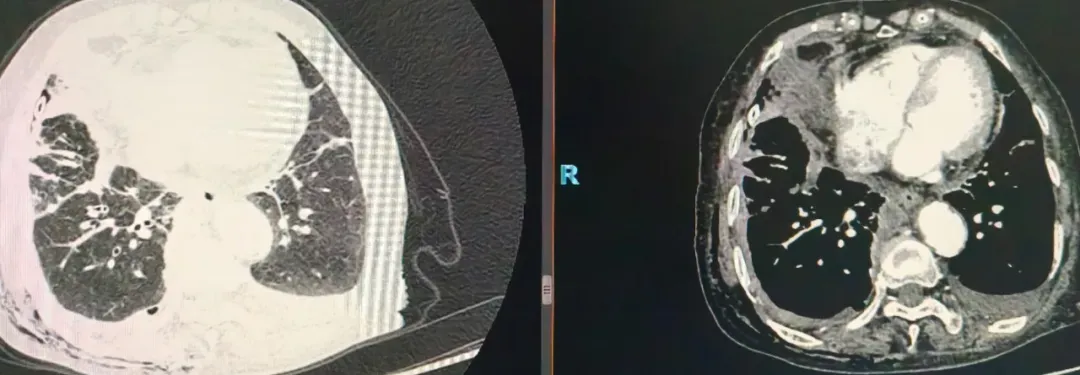

该患者因胸闷气短两月余、加重一周入院,本身患有心脏基础疾病及其他慢性基础病,经心电图、心脏超声等检查排除心脏器质性病变主导因素后,心病科第一时间邀请肺病科会诊。结合胸部影像学检查结果,专家团队判断患者症状由包裹性胸腔积液引发,需要通过胸膜活检明确积液性质,患者随即转入肺病科进一步治疗。

手术过程中,医生通过胸腔镜的高清视野,清晰定位包裹性积液的位置与范围,顺利完成积液清除操作,同时精准钳取病变胸膜组织送检。术中患者生命体征始终保持平稳。术后,在医护团队的精细化护理下,患者恢复状况较预期良好,胸闷、呼吸困难等症状得到缓解,可下床活动。